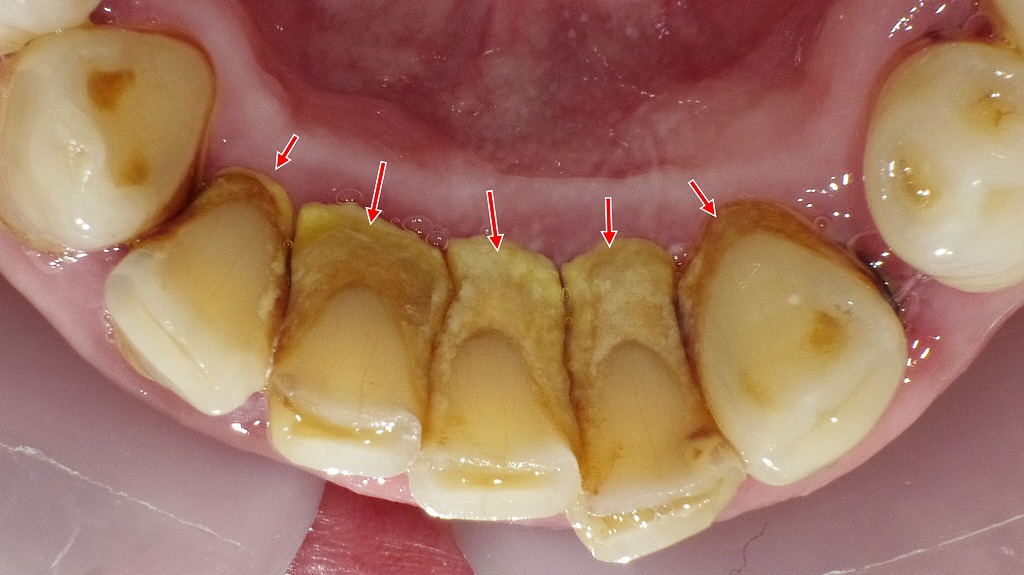

この画像は、歯の表面に「古くなった歯垢(プラーク)」が付着し、バイオフィルムが形成されている状態を示しています。

赤い矢印で示された部分に、黄色〜褐色を帯びた汚れが見られます。これは単なる着色ではなく、長期間除去されなかった歯垢が唾液中のカルシウムやリン酸と結合して硬化し、歯石化し始めているサインです。

🔍 詳細な解説

■ 上顎(左右の犬歯付近)

上の赤矢印部では、歯肉の境目に沿って茶褐色の汚れが見られます。

これは歯肉縁上プラークと呼ばれ、長期間放置されると歯石へと変化し、歯肉炎や歯周病の原因になります。

■ 下顎前歯部

下の矢印部では、歯の根元に厚いプラーク層が形成されています。

この部位は唾液腺の開口部に近く、ミネラル沈着が起こりやすいため、歯石が早期に付着しやすい部位です。歯肉が赤く腫れ気味で、炎症の兆候も見られます。

💡 対処法

- 毎日の正しいブラッシングとフロスによるプラーク除去

- **定期的な歯科クリーニング(3〜6ヶ月ごと)**で歯石とバイオフィルムを除去

- 着色が強い場合は、エアフローやスケーリングによるプロケアが効果的です